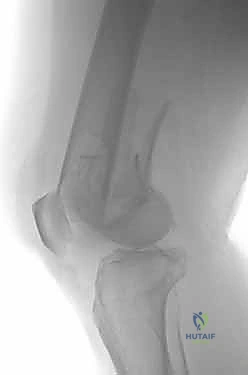

- الأشعة السينية (X-Rays): أخذ صور من زوايا متعددة (أمامي خلفي، وجانبي) لتحديد موقع الكسر ونوعه.

- الأشعة المقطعية (CT Scan): وهي ضرورية جداً في كسور عظم الفخذ البعيدة، خاصة إذا كان الكسر يمتد إلى داخل مفصل الركبة (Intra-articular fractures). تساعد الأشعة المقطعية الدكتور هطيف على بناء نموذج ثلاثي الأبعاد للكسر، مما يسهل التخطيط الجراحي وتحديد أماكن وضع المسامير بدقة.

المرحلة الثالثة: إرجاع العظم (Reduction)

هذه هي الخطوة الأكثر أهمية. يقوم الدكتور هطيف بإعادة القطع العظمية المكسورة إلى مكانها التشريحي الأصلي. إذا كان الكسر ممتداً داخل المفصل، يتم تثبيت السطح المفصلي أولاً باستخدام مسامير دقيقة لضمان سطح أملس يمنع الاحتكاك والخشونة مستقبلاً.